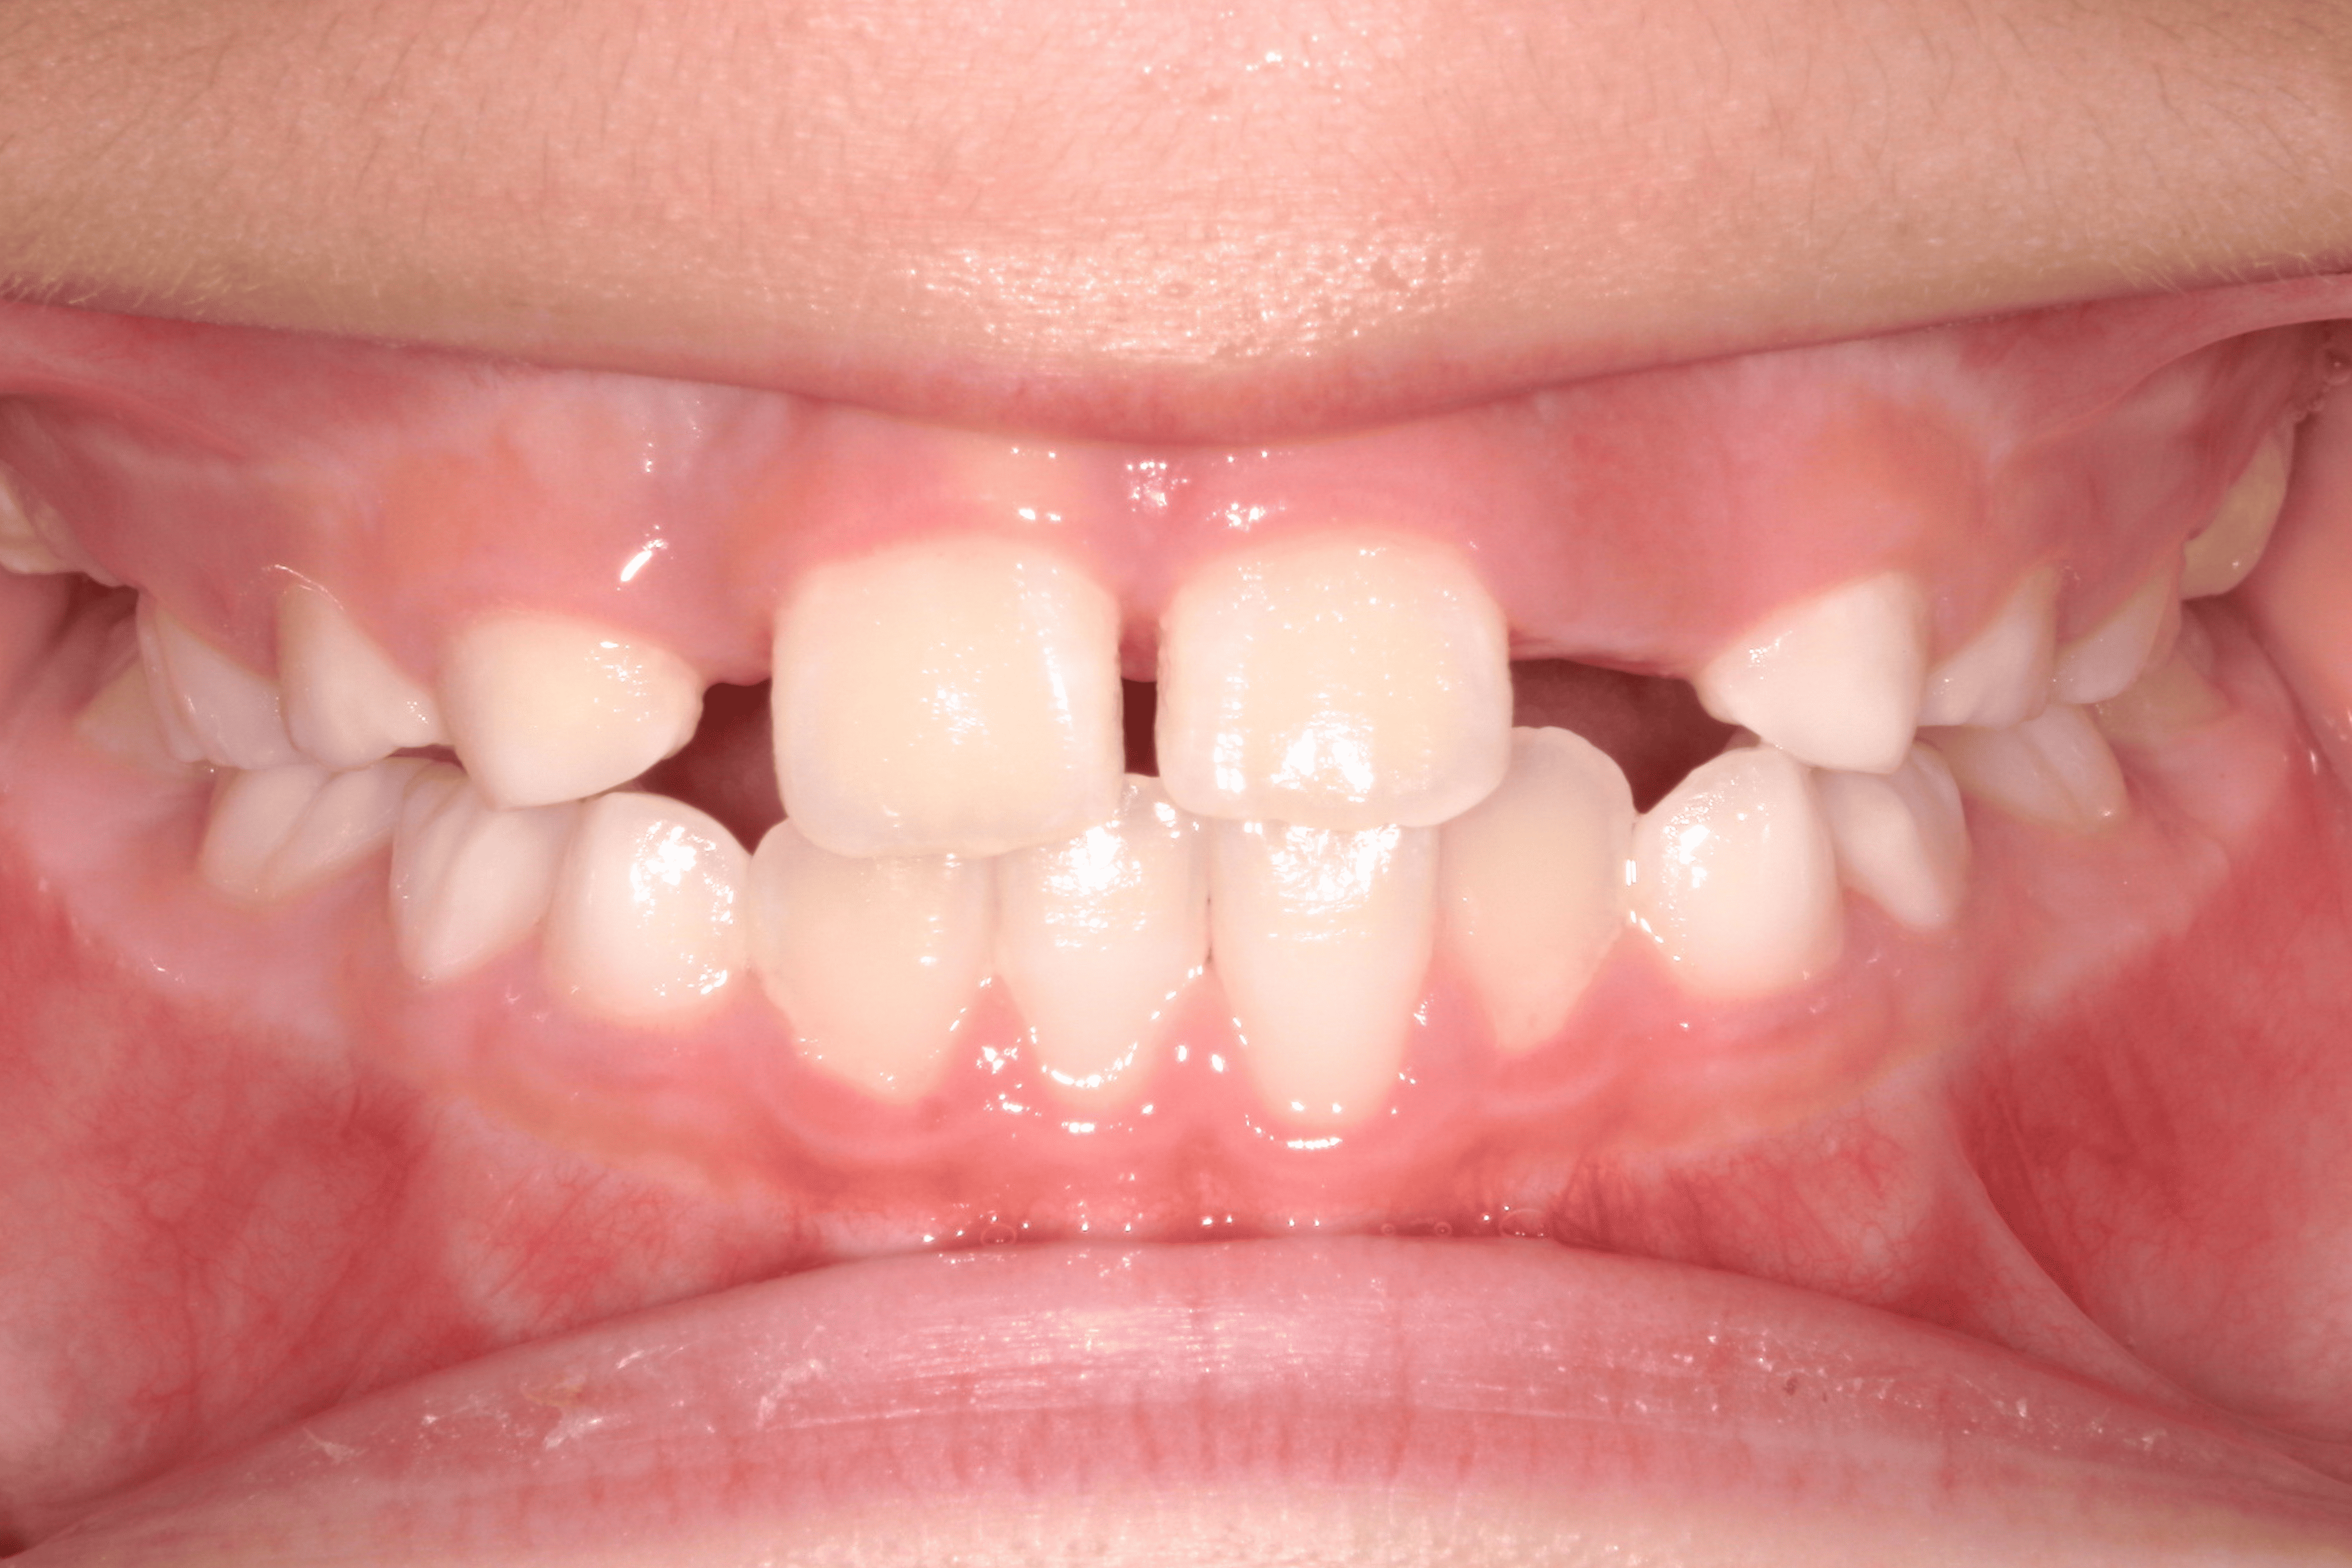

| 年齢・性別 | 8歳9ヶ月の女児 |

|---|---|

| 主訴 | 歯並びの乱れを気にされて来院された患者様です。将来的なスペース不足と歯のねじれ(翼状捻転)が懸念されました。 |

| 治療期間・回数 | 2年10ヶ月・19回 |

| 費用 | 430,000円(税別) |